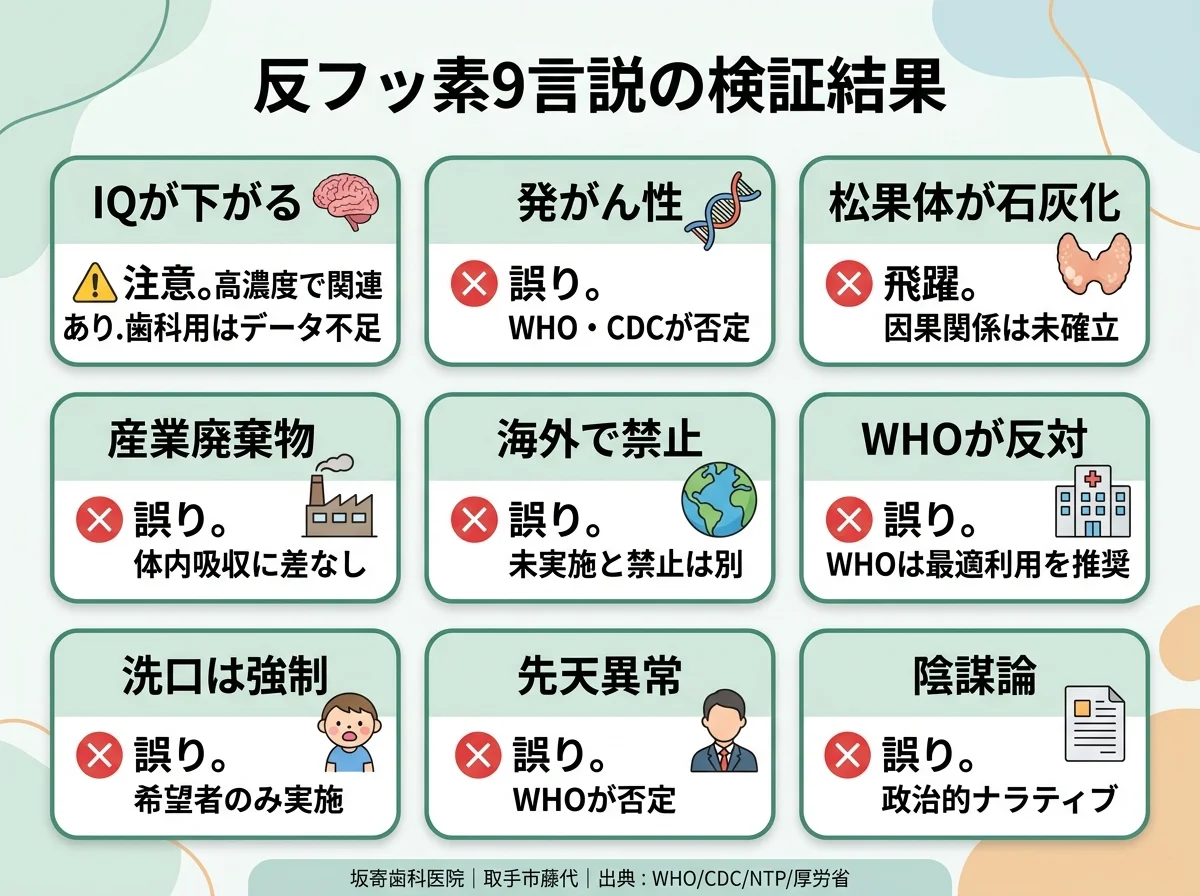

「フッ素は危険」は本当?歯科医が一次資料で検証する9つの反フッ素言説